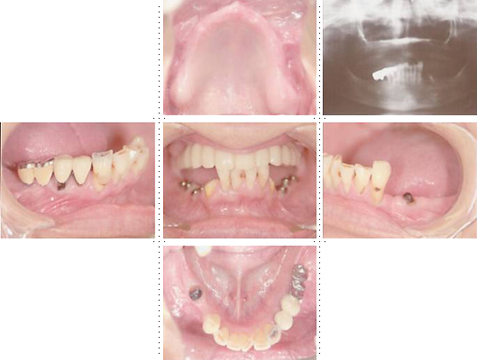

症例9

62才 男性

当院にてインプラント治療をされた患者さんからの紹介です。 一見すると残っている歯は多そうですが、実際はかなり歯周病が進行しており上下で15本の歯を抜かなければならない状態でした。 歯科治療における不安の1つとして、治療中に歯が無くては困るという相談をよく受けます。確かに噛めないのは不自由ですし、前歯であれば仕事など日常生活に大きな支障となります。しかし当院では抜歯した当日に義歯を装着できるシステムをとっており噛めない、見た目が気になるといった心配は全くありません。

このケースは局部床義歯の維持の為、犬歯を残し、抜歯後にすぐに入れられる義歯を使いながら、骨のあるところから適宜インプラントを埋入することで治療期間も負担も少なくてすみます。 インプラントは上顎8本、下顎8本を埋入しました。左下の奥は骨のしっかりしたところに傾斜埋入しました。 このような全顎ブリッジケースの咬み合わせは非常に難しいのですが、TEK(仮歯)を使った咬合採得方法にしてからはほぼ無調整でセットできるようになりました。 この咬合採得テクニックはインプラントセミナーで紹介し好評でした。